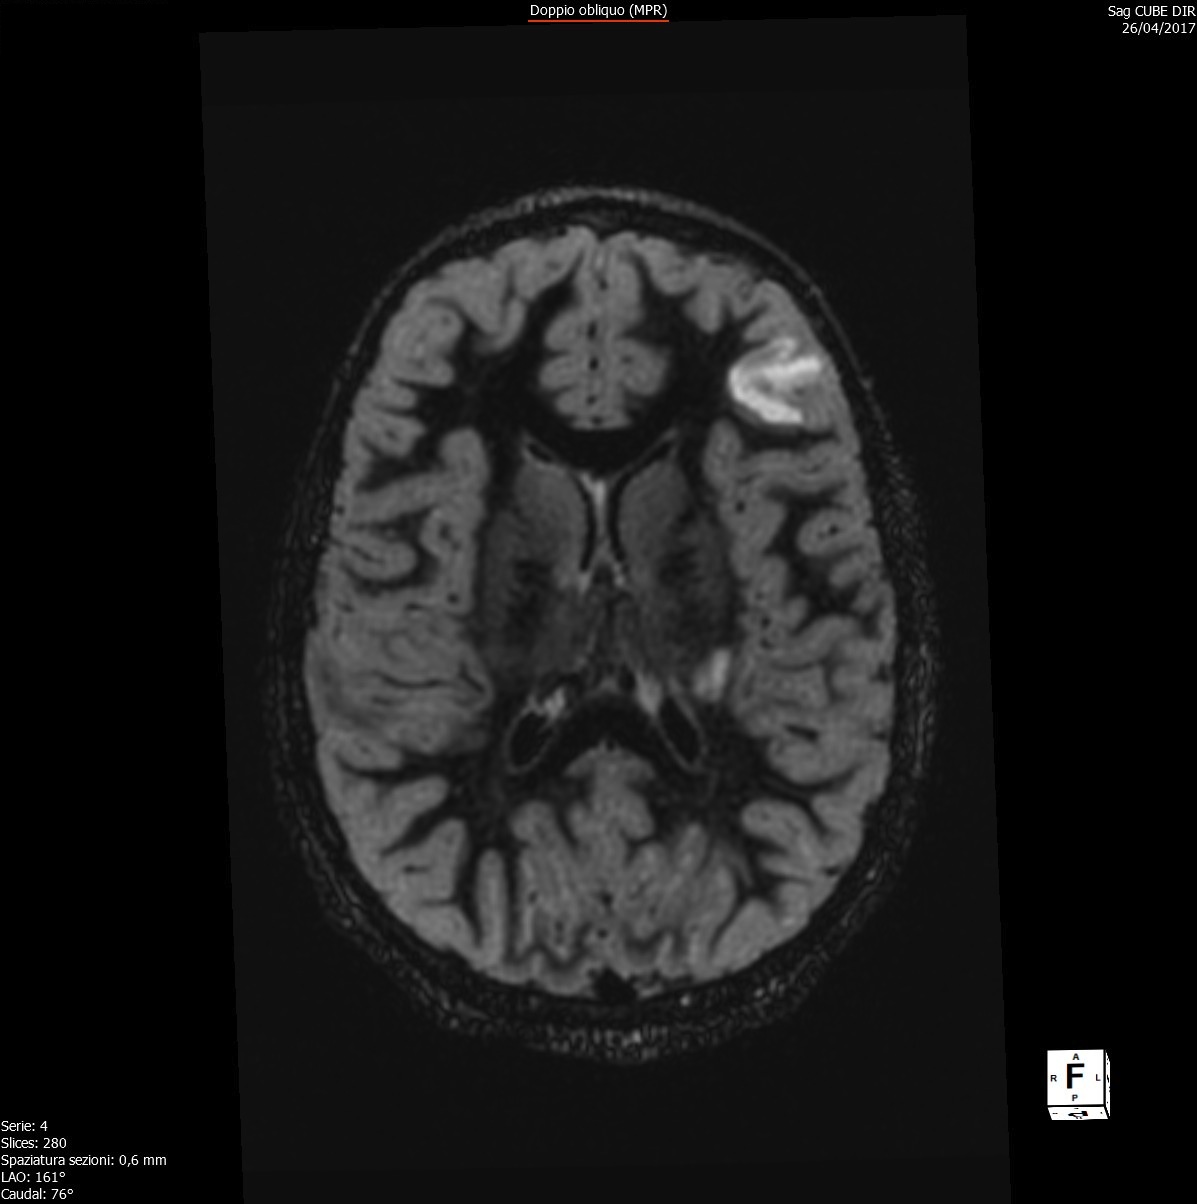

Durante il ricovero è stata eseguita RM di encefalo e midollo con mezzo di contrasto, che confermava la presenza di aree di alterato segnale già note a livello sovra- e sotto-tentoriale e il coinvolgimento midollare a livello di C1-C2, C4-C5, D10-D11 queste ultime con enhancement al contrasto, alterazioni compatibili con lesioni demielinizzanti ad andamento recidivante-remittente in fase attiva (Figure 1-3).